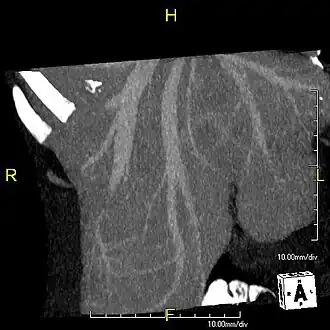

CT scan showing an adult liver in the axial plane

Organogenesis, the development of the organs, takes place from the third to the eighth week during embryonic development. The origins of the liver lie in both the ventral portion of the foregut endoderm (endoderm being one of the three embryonic germ layers) and the constituents of the adjacent septum transversum mesenchyme. In the human embryo, the hepatic diverticulum is the tube of endoderm that extends out from the foregut into the surrounding mesenchyme. The mesenchyme of septum transversum induces this endoderm to proliferate, to branch, and to form the glandular epithelium of the liver. A portion of the hepatic diverticulum (that region closest to the digestive tube) continues to function as the drainage duct of the liver, and a branch from this duct produces the gallbladder.[37] Besides signals from the septum transversum mesenchyme, fibroblast growth factor from the developing heart also contributes to hepatic competence, along with retinoic acid emanating from the lateral plate mesoderm. The hepatic endodermal cells undergo a morphological transition from columnar to pseudostratified resulting in thickening into the early liver bud. Their expansion forms a population of the bipotential hepatoblasts.[38] Hepatic stellate cells are derived from mesenchyme.[39]